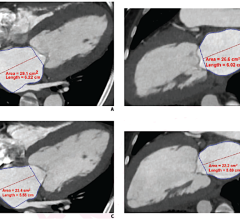

December 4, 2013 — Claron Technology, Inc. debuts version 3.0 of Withinsight Framework (WIF), an advanced platform that accelerates development of medical image visualization applications, at the 2013 Radiological Society of North America (RSNA) conference. This next-generation WIF includes enhancements in rendering, segmentation tools, and overall performance, providing Claron’s partners with advanced technology to meet their evolving needs. WIF 3.0 also serves as the foundation for Claron’s new clinical engines — algorithm solutions built to address specific clinically focused workflow needs. These engines identify medical image visual landmarks and segment organs and structures. At RSNA, Claron will showcase several clinical engines for liver segmentation, lesion segmentation, and spine landmark mapping, as well as time series and multi-modality registration.

Since its introduction in 2008, WIF has provided leading healthcare companies with the software toolkit for the development of more than 30 applications, ranging from 3-D ultrasound to MRI CAD, CTA spine and vessel analysis, PACS image reading and sharing, and therapy planning and guidance systems. Currently, these solutions are in use in thousands of clinical sites worldwide.

This latest product release delivers on Claron's commitment to continued WIF platform enhancement to meets its partners' evolving needs. “Claron partners with some of today's most innovative healthcare technology developers,” says Doron Dekel, Co-CEO, Claron Technology. “With on-going enhancements to WIF, we help ensure these companies maintain market leadership without the large software maintenance expenses that in-house development requires. In addition to many incremental improvements to performance and functionality, this release offers a number of leading-edge features, such as native 16bit rendering, enhanced segmentation tools, and powerful 3-D mesh editing tools. Claron is already using WIF 3.0 in its Nil family and surgical guidance products, with partner companies expected to follow shortly.”

The WIF platform provides visualization, segmentation, registration and navigation functionality to support development of standalone, thin-client and zero-footprint medical imaging applications. At the same time, its clinical engines provide an option to enhance existing applications by automating specific clinical tasks. Dekel points out that Claron’s clinical engines are provided to partners for customization and integration in their clinical application solution. “By offering clinical engines, Claron is providing functionality focused on automating specific clinical tasks. We expect these engines to expand Claron’s partner opportunities to companies that want to improve the workflow efficiency of one or more of their existing clinical applications,” says Dekel.